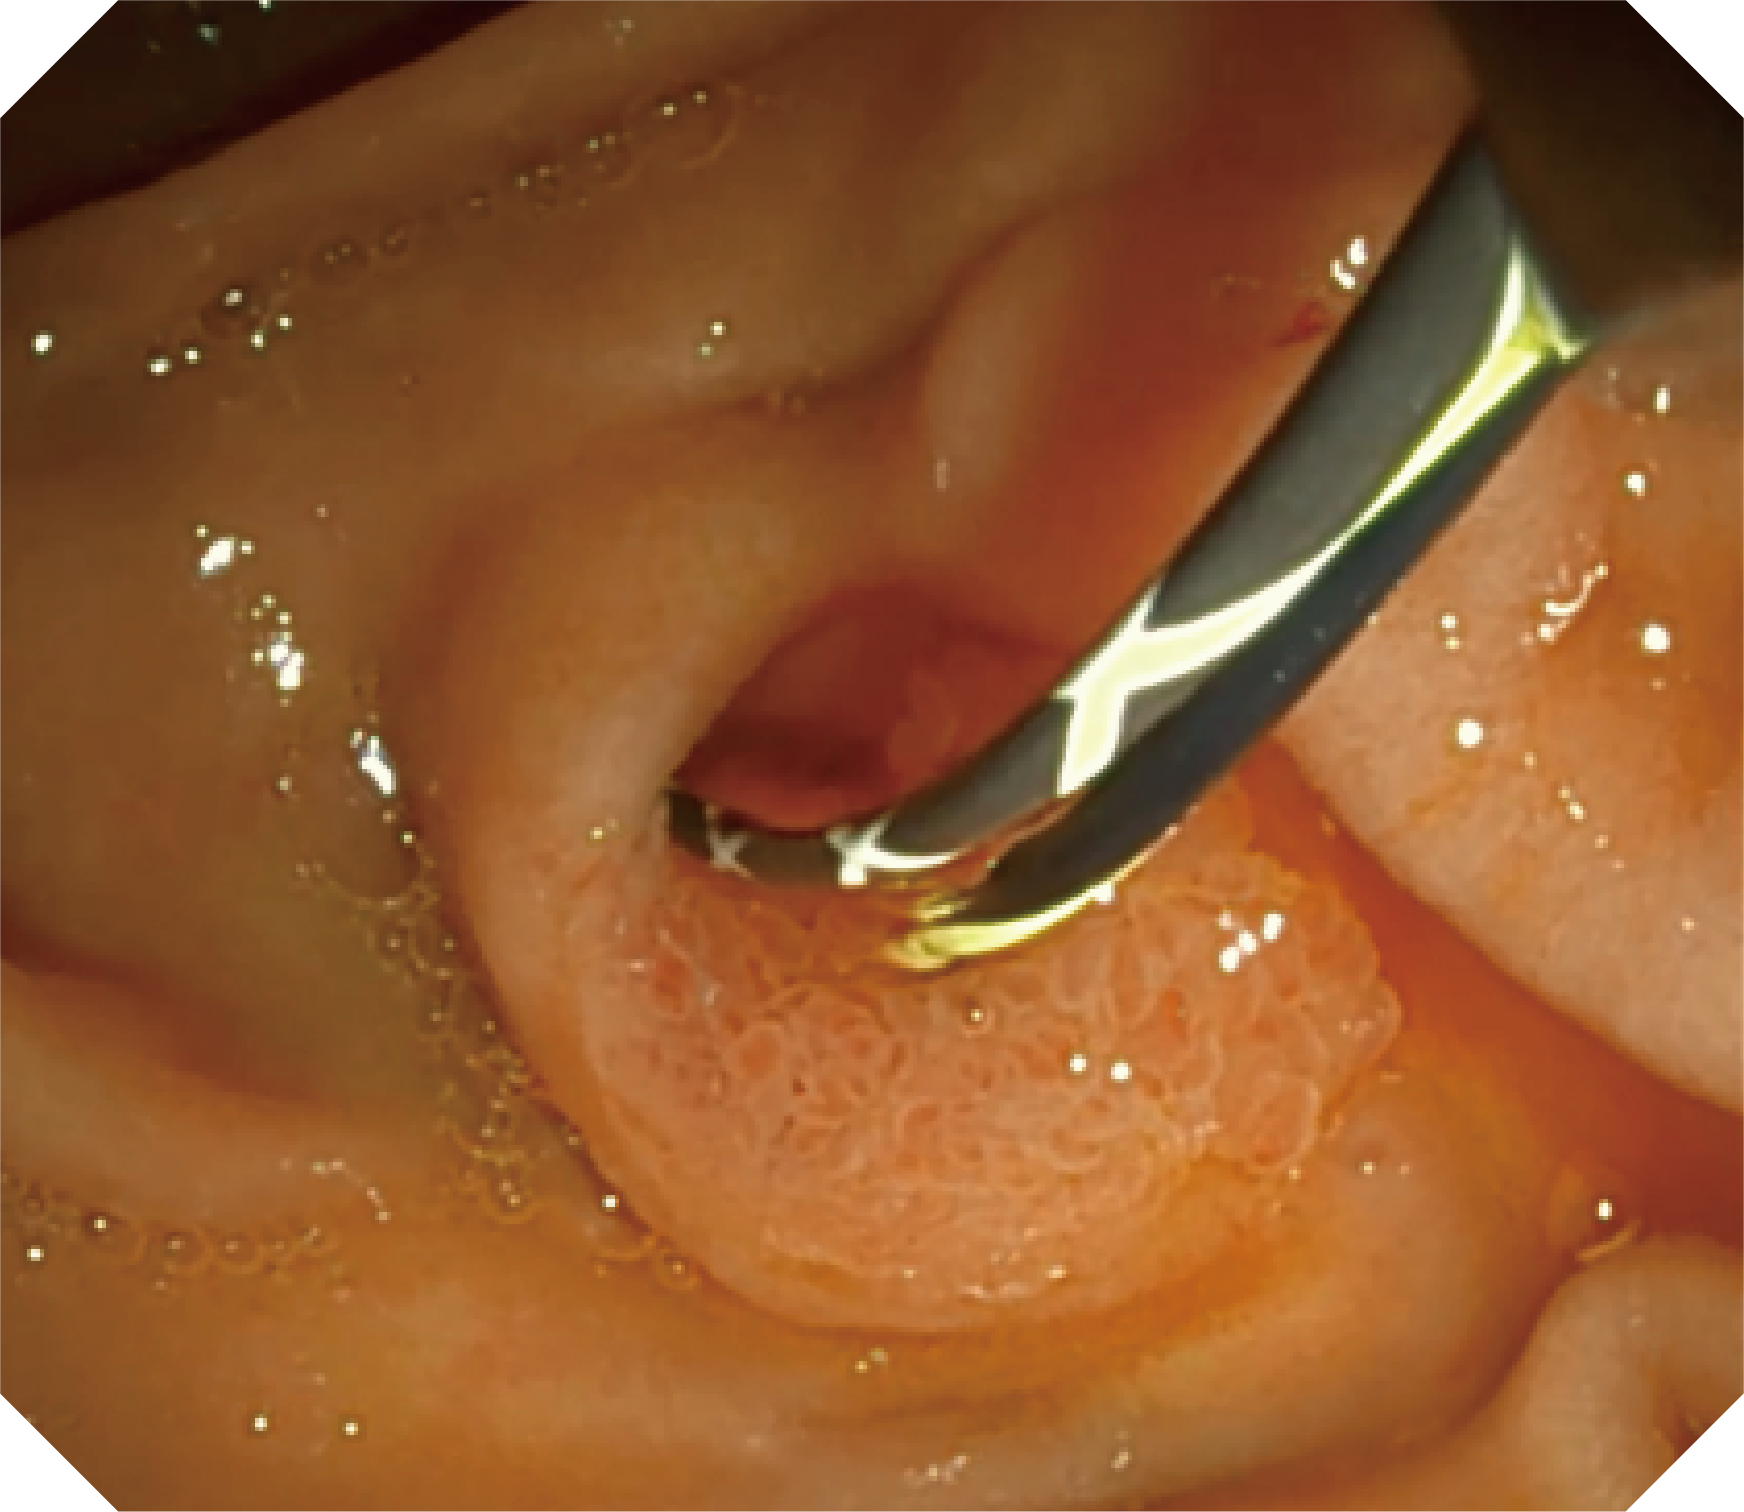

CMOS傳感器提供高清內(nèi)鏡視野 SFI/VIST光學(xué)染色技術(shù)凸顯病變區(qū)域

優(yōu)異的手術(shù)器械抬舉性

當(dāng)切開(kāi)刀伸出視野外時(shí),導(dǎo)向面引導(dǎo)其回歸視野